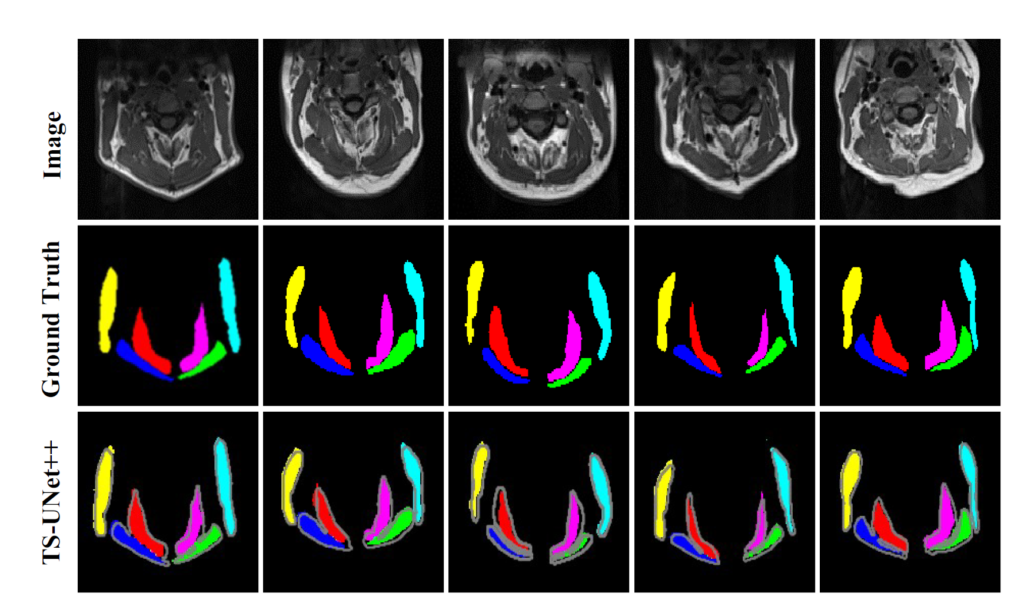

The following publication describes the algorithm and experimental results in more detail:

- Suman AA; Khemchandani Y; Asikuzzaman M; Webb AL; Perriman DM; Tahtali M; Pickering MR, 2020, ‘Evaluation of U-Net CNN Approaches for Human Neck MRI Segmentation’, in 2020 Digital Image Computing: Techniques and Applications, DICTA 2020, doi: 10.1109/DICTA51227.2020.9363385.

The following publications describe the algorithm and experimental results in more detail:

- Al Suman, A., Asikuzzaman, M., Webb, A. L., Perriman, D. M., Tahtali, M. & Pickering, M. R. (2020). A Deformable 3D-3D Registration Framework Using Discrete Periodic Spline Wavelet and Edge Position Difference. IEEE Access, 8, 146116-146133. doi: 10.1109/ACCESS.2020.3015504.

- Suman, A. A., Aktar, M. N., Asikuzzaman, M., Webb, A. L., Perriman, D. M., & Pickering, M. R. (2019). Segmentation and reconstruction of cervical muscles using knowledge-based grouping adaptation and new step-wise registration with discrete cosines. Computer Methods in Biomechanics and Biomedical Engineering: Imaging & Visualization, 7(1), 12-25. doi:10.1080/21681163.2017.1356751